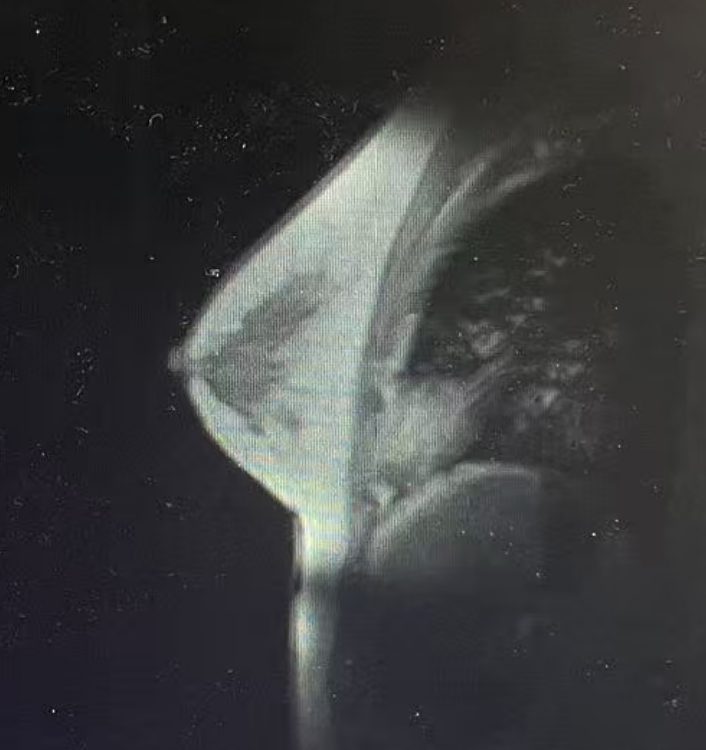

·乳腺钼靶

1、双乳腺体密度混合型ACR c型;

2、双乳小叶增生伴瘤化;右乳外上象限多发结节,考虑BIRADS 4B类,建议进一步MR检查。

图2乳腺DR结果